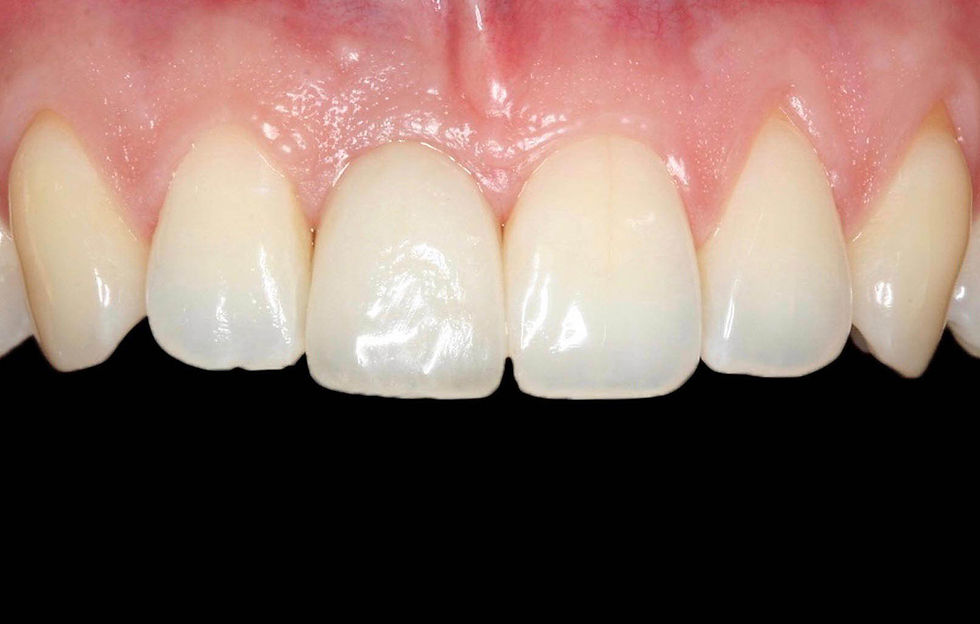

Frontal image at 12 months: progressive healing and soft tissue stability are confirmed.

Frontal control at 36 months: the alignment of the parabolas of elements 1.1 and 2.1. can be appreciated.